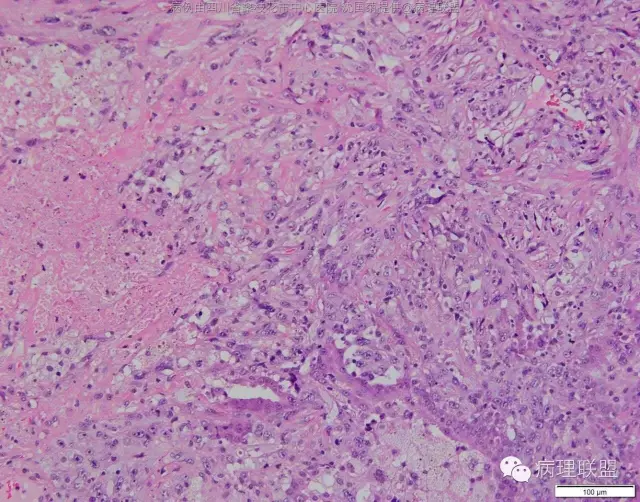

M/47 肺部占位,大小2*1*0.6cm(病例由四川攀枝花市中心医院 沈国菊提供,致谢!)

@张丽 免疫组化腺癌,鳞癌,神经内分泌,恶黑标记均为阴性,只有广谱CK跟Vimentin阳性,准备发大细胞癌

@沈国菊 肺大细胞癌的签发有时是个排他性诊断,我的体会:大细胞的标准:按淋巴细胞直径3倍来算,需要大于这个值,不能等于(从图给出,符合)。神经内分泌的标记(CD56 SYN CgA)完全阴性的可能性不是没有,建议重做试试;细胞的异型性大(符合);Ki67的指数高,应该非常高(您这里没有给出)。这仅仅是我个人体会,我说的不一定正确。

感谢您的精彩病例,采图非常漂亮,并且有标尺(特别赞)。魏老师,Ki-67阳性大于90%,送检7组淋巴结6/7见肿瘤转移。